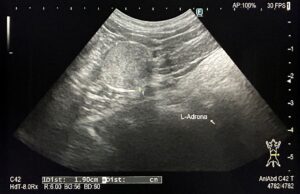

画像①:見えづらいが眼の中に腫瘤病変を疑う

超音波検査:虹彩・毛様体を起源とする腫瘤病変を疑う。下顎および内側咽頭後リンパ節への明らかな転移所見なし。

画像②:超音波検査にて腫瘤病変を確認